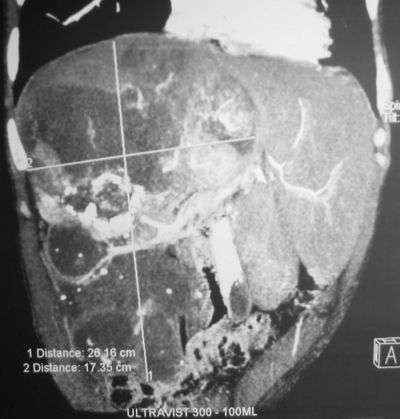

КТ органов брюшной полости.